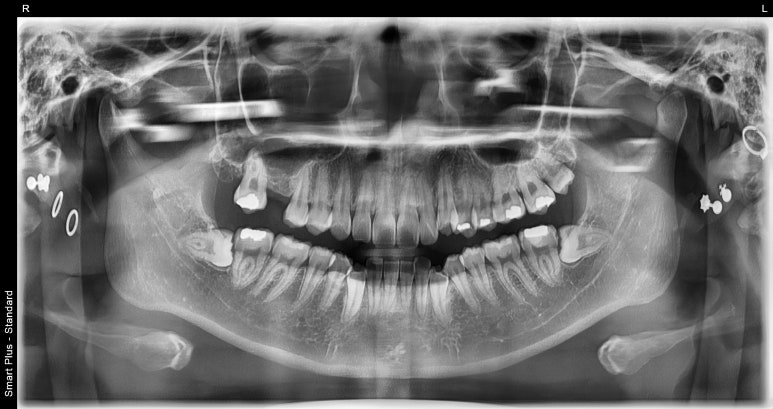

최근 저희 디데이치과에 방문해주신 환자분께서는 왼쪽 위 치아가 가끔 욱신거리고, 작은 어금니에 충치가 있어 치료를 원한다고 하셨습니다.

엑스레이 촬영 후 정확히 검진을 해보니 생각보다 문제가 심각해 작은 어금니 충치는 신경치료 후 크라운을 해야하는 상황이었고,

왼쪽 아래 큰 어금니 역시 크라운 치료가 필요한 상태였습니다.

오히려 환자분께서는 증상을 호소하지 않으셨던 오른쪽 위 치아는 상악동거상술을 포함한 임플란트 치료가 필요한 상태였고,

그밖에 왼쪽 위아래에 인레이 치료까지 해야하는 상황임을 모두 설명드렸습니다.

환자분께서는 설명을 들으시고 비용적인 부분때문에 부담되신다며 우선은 증상이 느껴지는 왼쪽부터 치료를 진행하고

경과를 살펴본 후 오른쪽도 마저 진행하고 싶다는 의사를 밝히셔서, 그렇게 치료하는 것으로 계획을 세워드렸습니다.